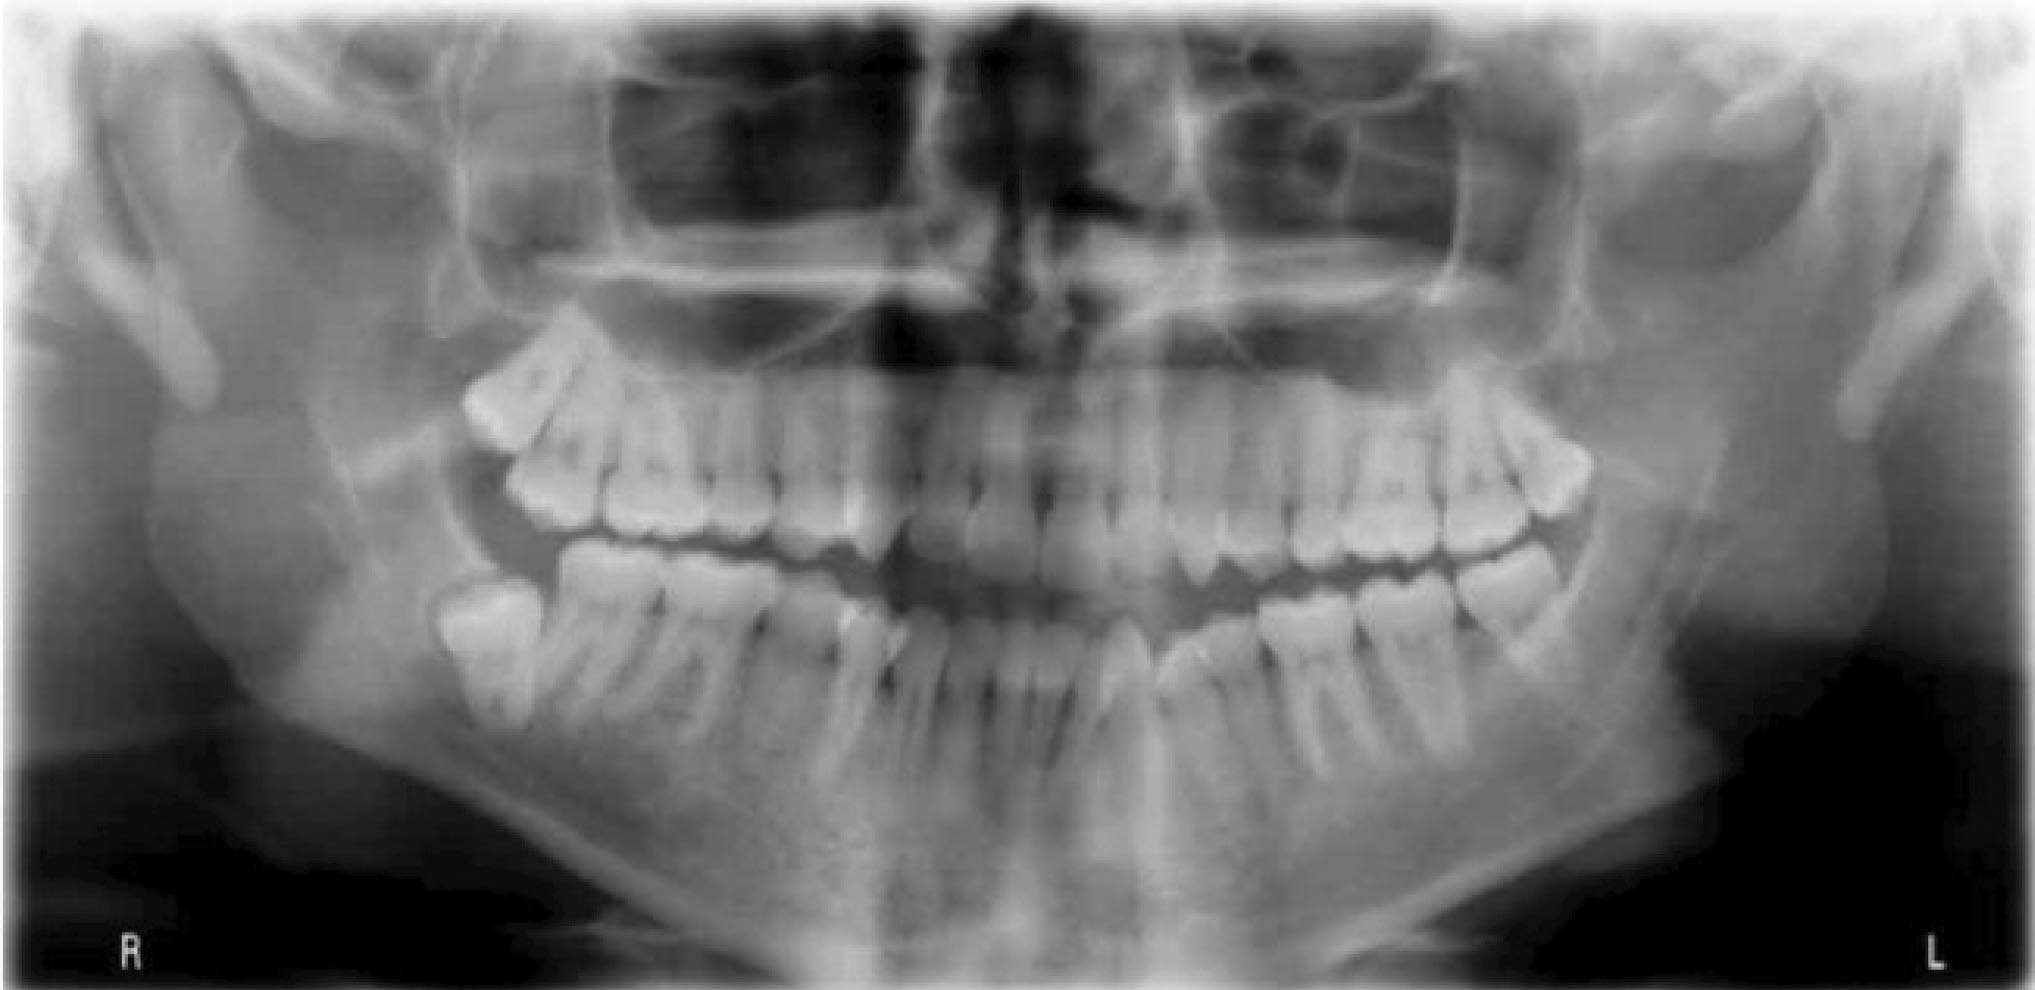

بیمار دارای اکلوژن کلاسIII با کرادینگ مختصر در هر دو فک است (شکلهای 121-۶ الی 123-۶). قرار بود که هم درمان ارتودنسی و هم درمان جراحی برای بیمار انجام شود. چون بیمار تمایلی به جراحی نداشت، لذا به راههای غیرجراحی بیشتر فکر کردیم. بخاطر شدت ناهنجاری در بُعد افقی تصمیم به کشیدن دو پرمولر پایین و استفاده از الاینر شفاف گرفتیم.

شکل 121-6

شکل 122-6

شکل 123-6

به این نتیجه رسیدیم که فک بالا را غیرکشیدنی به کمک اکسپنشن خلفی و استریپ دندانها درمان کنیم. در فک پایین هم با کشیدن ۴های پایین فضای کافی برای رفع کرادینگ و اصلاح اورجت بدست میآوریم.